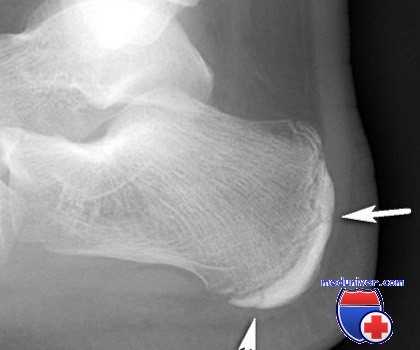

2. Рентгенография при болезни Севера:

• При рентгенографии изменения обычно отсутствуют

• Фрагментация и склерозирование апофиза заднего отростка пяточной кости достоверными признаками апофизита не являются:

о Могут быть обнаружены и у детей без клинической симптоматики

(Левый) Мальчик 12 лет. Выявлена клиническая симптоматика болезни Севера. При рентгенографии голеностопного сустава в боковой проекции определяются склерозированный и фрагментированный апофиз пяточной кости, а также зубчатый контур метафиза, что часто можно наблюдать и у детей без клинической симптоматики. Симптомы болезни Севера могут выявляться при тендинопатии ахиллова сухожилия, реакции апофиза на избыточную тягу ахиллова сухожилия или стресс-переломе пяточной кости.

• Рентгенография не позволяет достоверно подтвердить наличие данного заболевания:

о Выполняется, чтобы исключить другие причины развития болевого синдрома в пяточной области